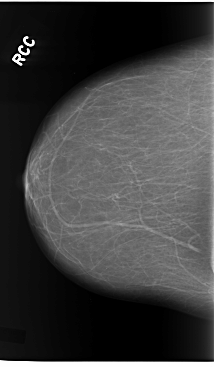

C_0119_1.RIGHT_MLO

RIGHT_CC LINES 5864 PIXELS_PER_LINE 3424 BITS_PER_PIXEL 12 RESOLUTION 50 NON_OVERLAY

RIGHT_MLO LINES 5840 PIXELS_PER_LINE 3248 BITS_PER_PIXEL 12 RESOLUTION 50 NON_OVERLAY